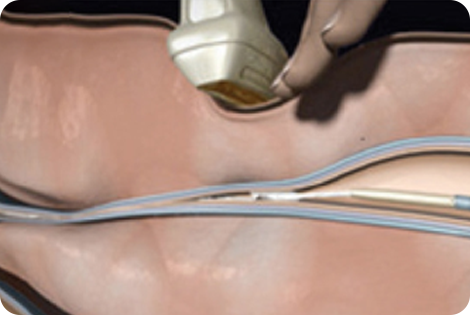

베나실은 인체 친화적인 의료용 접합제를

질환이 있는 원인 정맥에 주입하여

정맥을 폐쇄하는 하지정맥류 치료 의료기기입니다.

얇은 카테터(관)을

혈관에 삽입합니다

인체 친화적인

의료용 접합제를 주입합니다

해당부위를 압착합니다

혈관을 폐쇄하여 붙입니다